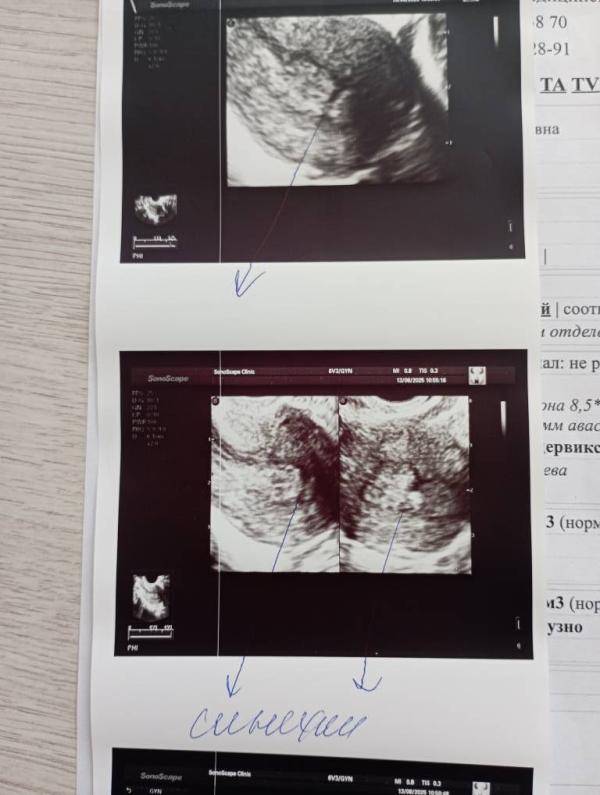

Синехии на УЗИ: могут ли исчезнуть к следующему обследованию?

На 38дц нашли на узи синехии, назначили повторно УЗИ на 7-8дц. Может ли быть такое, что их может и не быть, на повторном узи? И делал ли кто нибудь узи у Мадины Сайгидгусейновны, в клинике " Мой доктор? "

Надо переделать в новом цикле на 5-7 день цикла.

Да, бывают ошибки, узи это никогда не 100%.

Кто знает может это и не синехии а показалось )

От самого узиста тоже зависит

Если конечно оно есть их лучше удалять